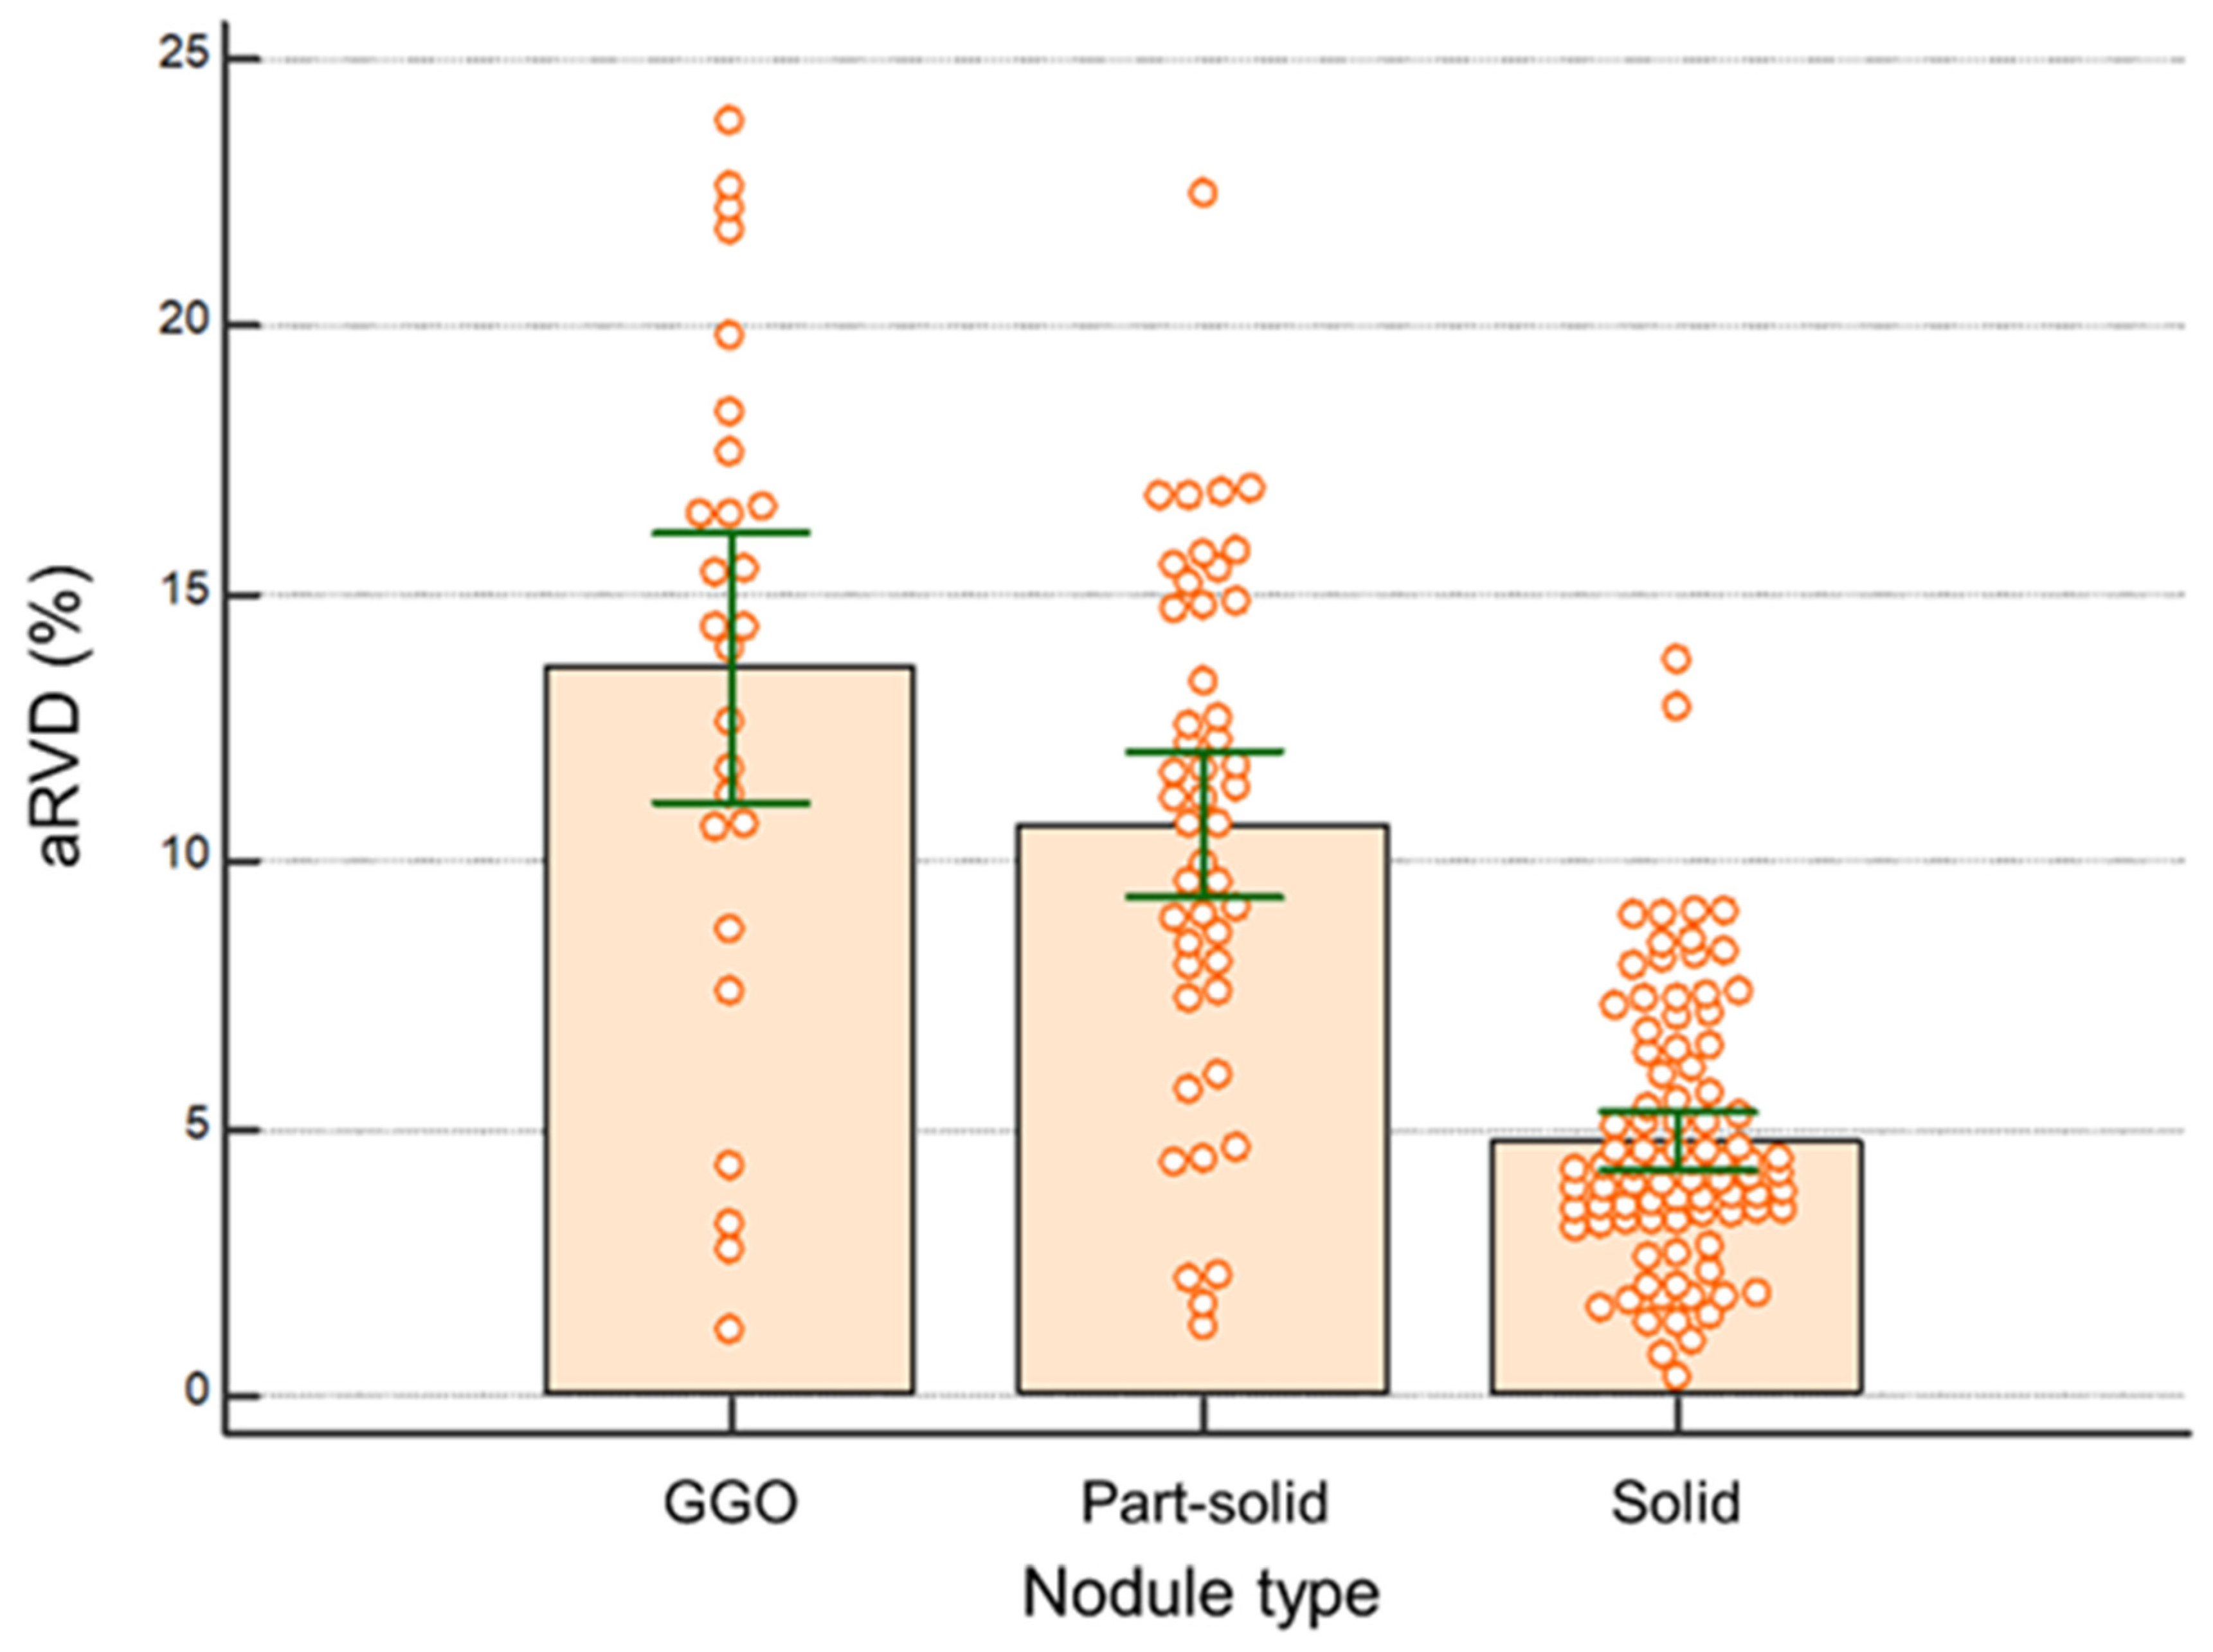

3.4. Subjective Image Quality Analysis between SSSP and HSHP

| Nodule Classification (n = 163) | aRVD | p-Value |

|---|---|---|

| Nodule location | 0.486 | |

| Upper lobes | 7.3 ± 5.6 (5.9–8.7) | |

| Middle lobes * | 9.0 ± 5.9 (5.8–12.1) | |

| Lower lobes | 8.1 ± 5.1 (7.0–9.2) | |

| Nodule type | <0.001 | |

| Ground glass opacity | 13.62 ± 6.3 (11.1–16.2) | GGO vs. part-solid 0.009 |

| Part-solid | 10.7 ± 4.7 (9.3–12.1) | Part-solid vs. solid <0.001 |

| Solid | 4.8 ± 2.5 (4.2–5.3) | GGO vs. solid <0.001 |

| Nodule volume (mm3) | 0.177 | |

| <500 | 8.3 ± 5.0 (7.2–9.4) | |

| 500–1000 | 8.6 ± 6.1 (6.3–11.0) | |

| >1000 | 6.8 ± 5.5 (5.2–8.3) |